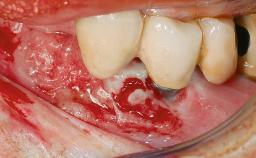

Management of a Fractured Implant Supporting a Screw-retained Metal-ceramic Restoration

The fracture of an implant after it has been restored is one of the most severe complications. It most frequently occurs in partially edentulous jaws (1.5%). Most implant fractures involve implants with a diameter of 3.75 mm made of commercially pure titanium (Eckert 2010). Unfortunately, many cases are not reported or documented by the clinicians involved in resolving the problems created by the fracture. This case report describes the management of an implant fracture at site 36 in a middle-aged male patient. The implant had been restored with a screw-retained metal-ceramic crown.